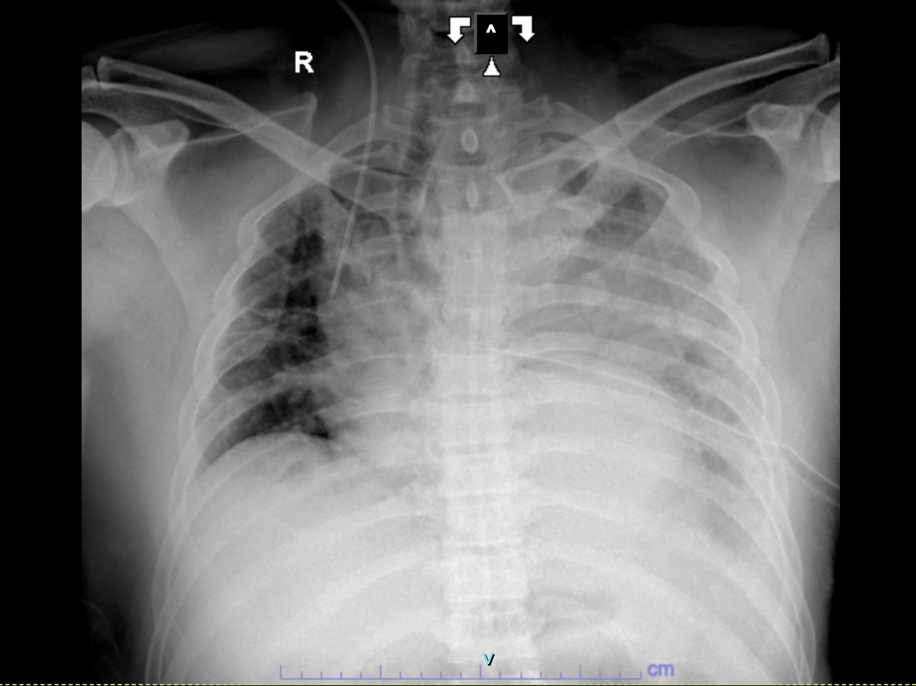

Chest X-ray showed total opacification of the left hemithorax with mediastinal shift. Non-contrast CT revealed a massive pleural collection obscuring the aortic contour, suggesting hematothorax. After stabilization and VATS decompression, CT angiography demonstrated a DeBakey type III (Stanford B) dissection from the arch to the left iliac artery with aneurysmal dilation and impending rupture distal to the left subclavian artery.